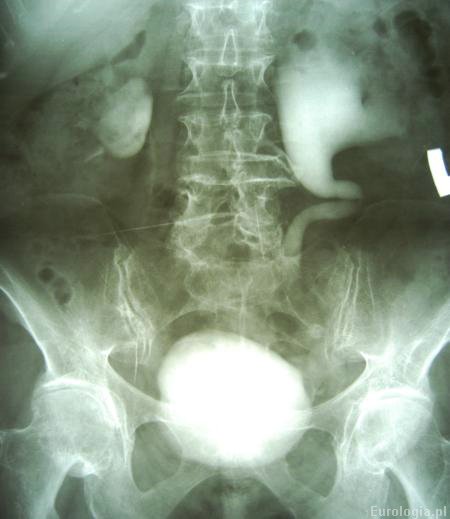

Wodonercze rozpoznawane jest na podstawie badań obrazowych. Badanie USG jamy brzusznej jest podstawowym badaniem obrazowym w diagnostyce wodonercza. W badaniu USG określany jest stopień zastoju moczu w UKM - wymiar przednio - tylny miedniczki i grubość warstwy miąższowej - kory nerki. Do obrazowania wodonercza oprócz ultrasonografii wykorzystuje się także tomografię komputerową, urografię i rezonans magnetyczny. Scyntygrafia jest badaniem, które pozwala ocenić czynność nerki. W czasie badania pacjent otrzymuje dożylnie radioaktywny znacznik a następnie ocenia się szybkość jego wydalania przez nerki.

Fot. Wodonercze lewostronne - urografia